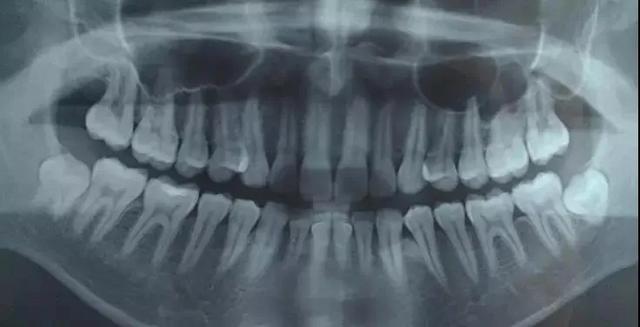

2.侵犯邻牙:通常患者不自知,而由牙医以X光诊断得知。通常智齿萌发的空间不足,而会倒在第二大臼齿上,因而造成第二大臼齿清洁不易,甚至是牙齿部分吸收的现象,造成患者不舒适或牙疼。

6.阻生齿:通常这是最讨厌的一种,牙医会觉得很难搞定,但病人却不一定有感觉,因此忽略了。这一种类型的牙齿,通常埋在齿槽骨的里面,如果会痛,或是诊断会有病灶发生的时候,就需要拔除了。